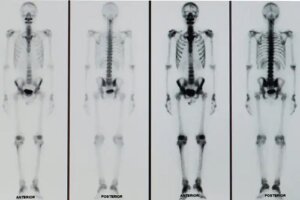

Examenele imagistice sunt instrumente care ajută personalul medical să înțeleagă starea de sănătate a mai multor organe și sisteme. O scanare osoasă este un test care oferă imagini clare ale scheletului și ale posibilelor patologii prezente la nivelul acestuia.

Scanarea osoasă este un test care aparține medicinei nucleare, deci implică utilizarea de substanțe radioactive. Substanțele administrate sunt cunoscute ca markeri și vor emite mici cantități de radiații gamma care vor fi captate de un computer special.

Markerii trebuie injectați într-o venă mare pentru a călători în tot corpul. Oasele vor absorbi radiația gamma pe măsură ce markerii se mișcă. Proliferarea anormală a celulelor osoase va duce la o absorbție crescută a radiațiilor.

Rezultatele unei scintigrafii osoase sunt disponibile într-un timp scurt și trebuie analizate de un medic specialist. Substanța marker se întinde uniform pe oasele care nu prezintă niciun tip de alterare.

Pe de altă parte, zonele cu o alterare a celulelor osoase prezintă modificări. În acest sens, se pot observa zone mai deschise sau mai întunecate decât restul oaselor.